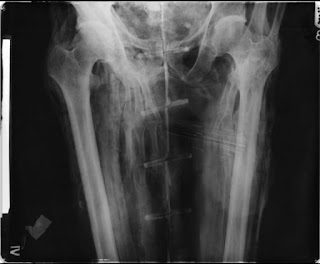

In September 1851 Padiamun’s mummy was unwrapped at Edgeworth Manor by a surgeon named H W Rumsey, Esq. The wrappings were roughly replaced after the examination in 1851 and then rewrapped in 1976. There are several bags of excess bandages. The mummy was X-rayed in 1967 and CT scanned in 2012 . PHK Gray who led the radiograph study of Liverpool's mummies in 1967 noted that the treatment of Padiamun's body is not normally found after the beginning of the Twenty-sixth Dynasty and suggested embalmment during the Twenty-first and Twenty-second Dynasties. A sample of resin was taken from the top of the cranium in 1999 for analysis which revealed the contents to be: 61% fat/oil, 0.2% coniferous resin, 1.5% balsam